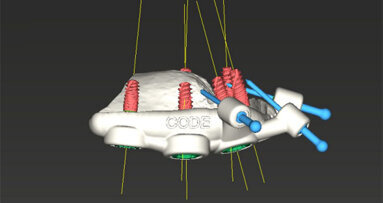

Ze zvířecího modelu žebra odstranili dostatek kosti, aby odkryli periost, který sloužil jako zdroj kmenových buněk a cév pro implantaci štěpového materiálu do formy. Testované skupiny dostaly rozdrcenou kost žebra a syntetické materiály na bázi fosforečnanu vápenatého tvořící biologicky kompatibilní základ štěpu.

Forma s otevřenou částí žebra pro vytvoření těsného rozhraní zůstala na místě po dobu devíti týdnů, pak byla odebrána a přenesena do místa defektu, kde nahradila distanční vložku. Na zvířecích modelech se nová kost propojila se starou a kolem narostly měkké tkáně a oblast pokryly.

„Rozhodli jsme se použít žeber, protože jsou snadno přístupná a jsou bohatým zdrojem kmenových buněk a cév, které proniknou do štěpu a vrostou do nové kostní tkáně, která se přizpůsobí pacientovi,“ uvedl Mikos. „Není zapotřebí žádných exogenních růstových faktorů nebo buněk, které by komplikovaly proces zákonných schvalování a přechod ke klinickému použití.“